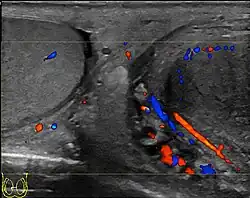

- Ultrasonido testicular

- Lefort C; Thoumas D; Badachi Y; etal (julio de 2001). «Orchites ischémiques: À propos de 5 cas diagnostiqués en écho-Doppler couleur» [Ischemic orchiditis: review of 5 cases diagnosed by color Doppler ultrasonography]. Journal De Radiologie (en francés) 82 (7): 839-42. PMID 11507447.

- Chung JJ, Kim MJ, Lee T, Yoo HS, Lee JT (septiembre de 1997). «Sonographic findings in tuberculous epididymitis and epididymo-orchitis». Journal of Clinical Ultrasound 25 (7): 390-4. PMID 9282805. doi:10.1002/(SICI)1097-0096(199709)25:7<390::AID-JCU7>3.0.CO;2-5.